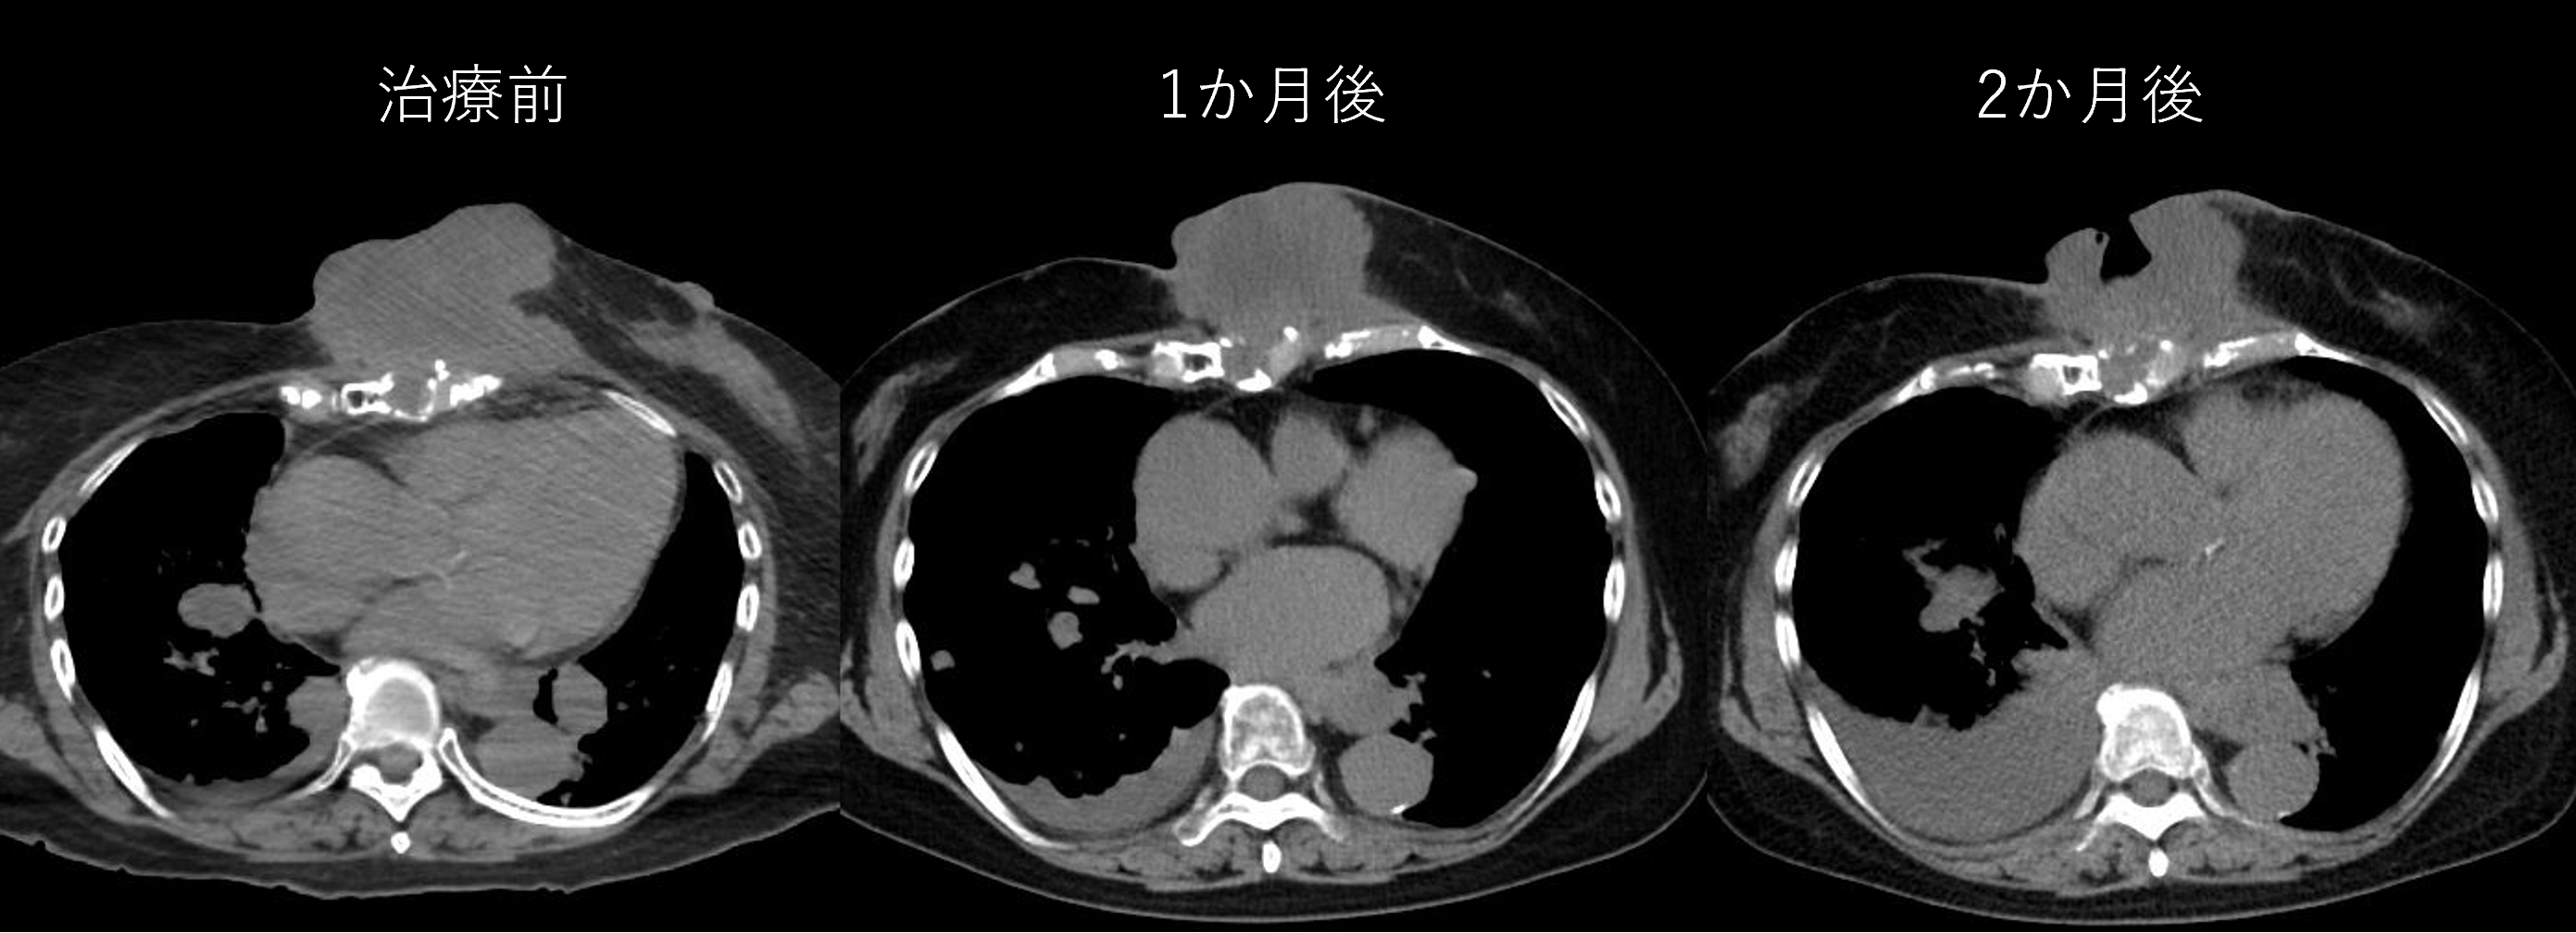

10月に行われた4例目の60日後の診察が行われました。この4例目はかなり大きめの腫瘍かつ肺転移などがある患者さんです。1か月後のCTではあまり変化はなかったのですが、2か月後では内部に空洞ができ、かなり腫瘍は小さくなっておりました。また胸水の増加などが認められますが、全身状態に大きな変化はありませんでした。

4例目は今までの症例とは異なり、かなり大きめの腫瘍に対してBNCTを施行させていただきました。かつ、本研究では転移がある方を転移があるからという理由だけで除外は行わないこととなっており、かなり広範な転移がある方です。1か月後のCTではあまり変化はありませんが、本人の自覚としてはかなり小さくなっており、右乳房と腫瘤の間に指が入るようになった、体調も良いと喜んでおりました。

なお、本研究では本人の自覚や視触診による効果判定は行わないため、また今後のMRIやCTで違う結果になる可能性があります。4例目ではGrade1の副作用、またほかの3例についてもGrade2までの副作用ですが、今後の経過では発生する可能性はあります。